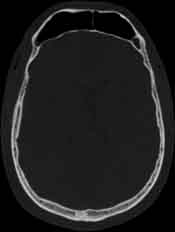

Visible Human male: Sectio transversalis 1078

CT